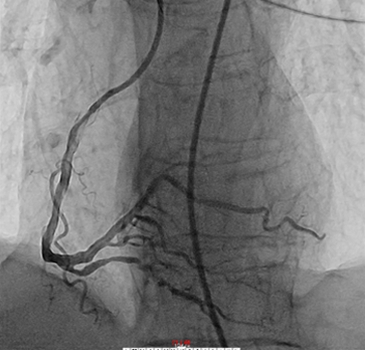

今年1月,患者梁伯因反复活动胸闷气短到我院住院治疗。梁伯是个老烟民,在入院后完善相关检验检查后,考虑诊断为不稳定型心绞痛。随后在进一步完善冠脉造影后,提示梁伯的右冠重度钙化,全程管腔不规则狭窄,其中远端狭窄达85%,需要尽快进行介入手术治疗。于2月23日进行手术后,造影显示冠状动脉右冠远端有明显狭窄伴钙化。经李龙虎主任医师手术团队讨论后,决定为梁伯采用Shockwave血管内冲击波钙化碎裂术,经过5个周期的冲击波治疗,精确碎裂冠状动脉内膜和中膜下钙化病灶,随后顺利植入支架。

▲ 使用IVL之后

手术过程:送Shockwave 2.5-12mm C2球囊至RCA远段病变处,压力充盈至4ATM,触发10个冲击波脉冲松解钙化斑块,然后充盈压升至6ATM维持10s对病变行低压球囊扩张成形,然后球囊泄压10s恢复靶血管而管灌注,此为1个治疗周期。重复上诉操作,总计2.5-12mm C2球囊输送5个治疗周期。

此次通过Shockwave IVL技术的实施,精准治疗血管钙化,为患者植入支架提供更好的的管腔。